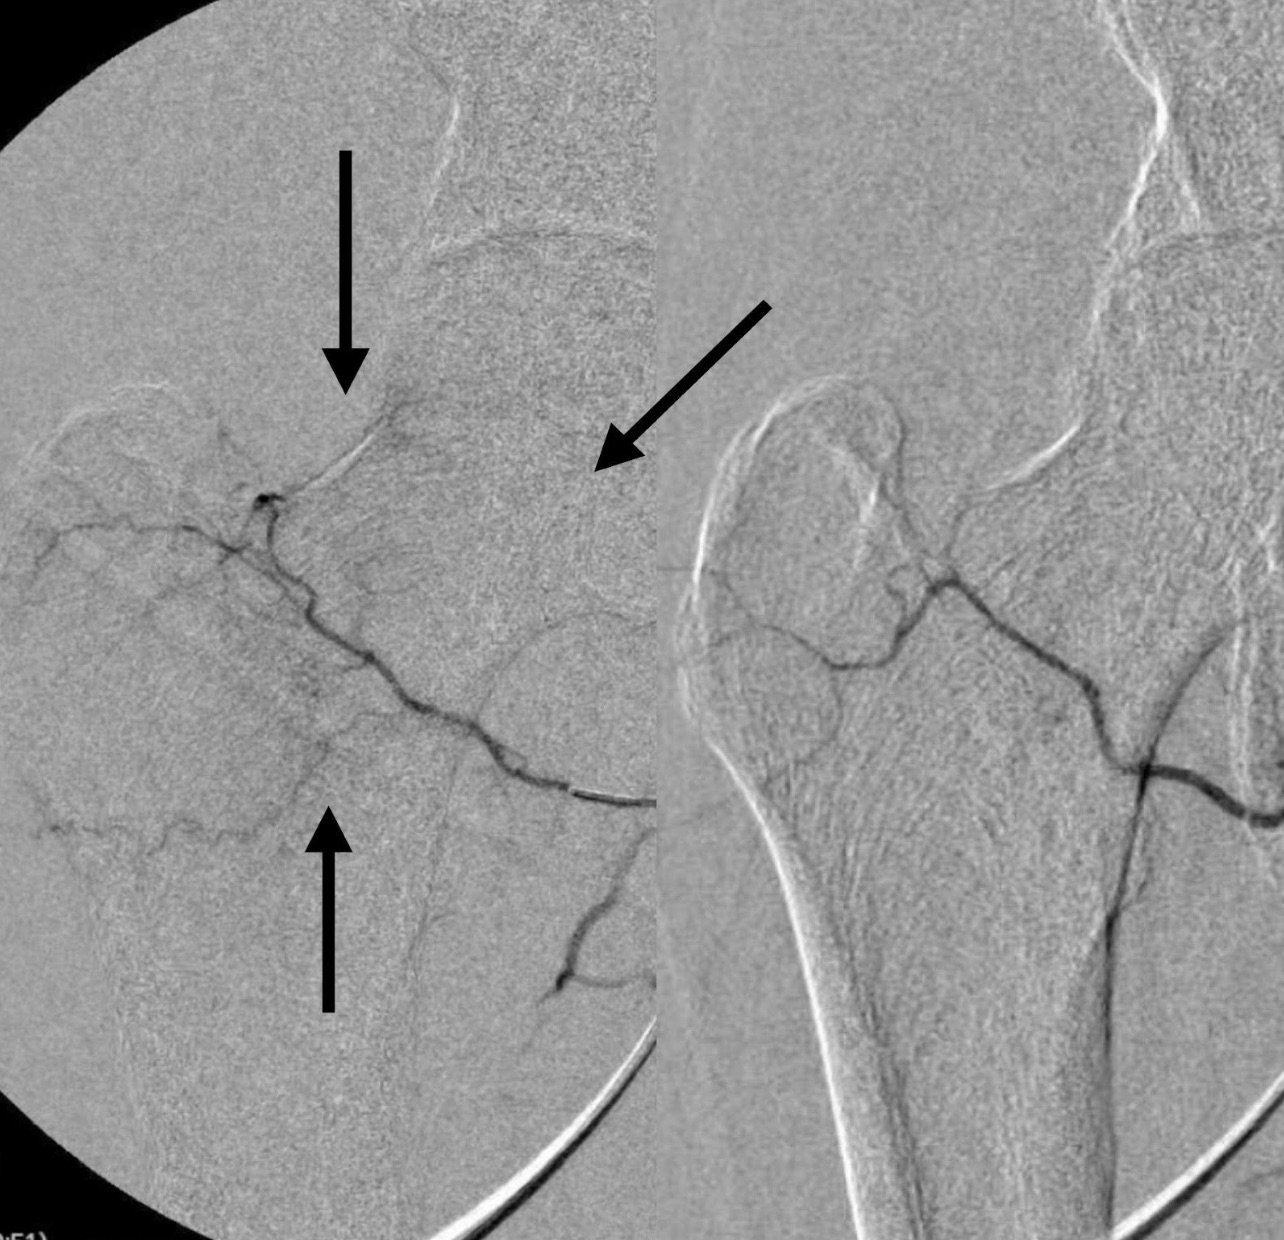

Arrows on the left pointing to the hypervascularity that causes pain in patients with Hip arthritis.

- Guided Navigation: Using fluoroscopic guidance (real-time X-ray), the catheter is navigated to the blood vessels supplying the inflamed area of the hip.

- Embolization: Tiny particles or beads are released through the catheter to block the blood vessels, reducing blood flow to the inflamed tissues.